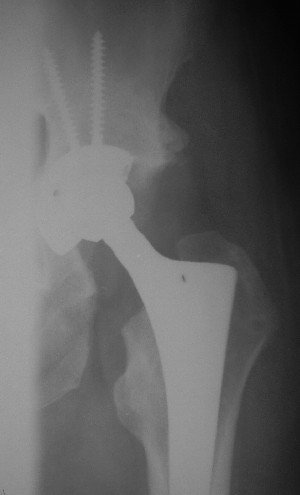

После протезирования прямой 5/04/04

|

После протезирования боковой 5/04/04

Больной 18 мая 2003 года в автоаварии получил перелом левой вертлужной впадины, вывих бедра. Госпитализирован в один из стационаров области.Вывих вправлен. В последствии бедро вывихивалось еще дважды. На консультацию был представлен снимок от 19.05.03г., больной переведен к нам 3.06.03г. Снимок при поступлении - перелом впадины, задне-верхний вывих бедра. 05.06.2003 г. выполнено открытое вправление вывиха левого бедра и остеосинтез стенки вертлужной впадины двумя винтами. Послеоперационный период без осложнений. Объем движений в левом тазобедренном суставе восстановился полностью. Выписан на амбулаторное лечение в удовлетворительном состоянии с рекомендациями 3 месяца ходить на костылях без нагрузки на оперированную конечность. На контрольных рентгенограммах левого тазобедренного сустава 13.10.2003 г. - признаки консолидации перелома; плотность, форма головки и состояние суставных поверхностей удовлетворительные. Разрешена дозированная осевая нагрузка, на конечность с использованием дополнительной опоры. 19.12.2003 г. больной обратился с жалобами на боли в левом тазобедренном суставе. На рентгенограммах левого тазобедренного сустава 19.12.2003 г., 20.02.04г. - асептичекий некроз головки бедра. 5.04.04г. - эндопротез. Сейчас ходит без трости, не хромает. Особенность эндопротезирования - при удалении винтов прослежена линия перелома заднего края впадины и предложено установить чашку несколько меньшего диаметра, чтобы она была покрыта несломанной частью.